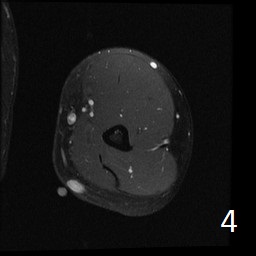

Angiolipoma is a subcutaneous benign tumor, made up of mature fat and blood vessels that often presents as multiple lesions. It sometimes arises intramuscularly. The incidence may be associated with familial heritage, close to 5% of the cases. Angiolipomas often arise in young patients, shortly before puberty, and are rarely seen in younger children or older adults. Angiolipomas often present as single or multiple subcutaneous tender to painful nodules (especially multiple ones). The pain may decrease as the lesion ages. No preference for ages or gender. Sites more commonly affected are the upper extremity and trunk, but rarely can affect head and neck region. MRI shows homogeneous and well circumscribed lesion, with intermediated signal on T1w (Fig. 1) and increased signal on T2W (Fig. 2). On fat suppress sequences the tumor may not suppress completely necause of its vascularity (Fig. 3). There is significant enhancement post contrast images (Fig. 4). On gross pathology the mass is a circumscribed, yellow-red nodular mass due high fat content and blood vessel proliferation. Microscopically, shows mature fat cells separated by branching network of small blood vessels, more prominent in subcapsular areas; there are usually associated fibrin thrombi (important sign). Adipocytes and interspersed vascular structures are seen, lined by elongated endothelial cells. These cells are irregular, and fingerlike extensions surrounded by periytes. Angiolipoma is a benign mass. It does not exhibit aggressive behavior. It rarely shows recurrence after resection. The treatment is complete surgical excision.

Fig. 1-4: Axial MRI of the arm shows a well circumscribed mass with intermediate signal on T1W (Fig. 1), and increased in T2W (Fig. 2). Fig. 3 Axial T1W FS shows a lesion and moderate intense on T1WFS post contrast (Fig. 4).